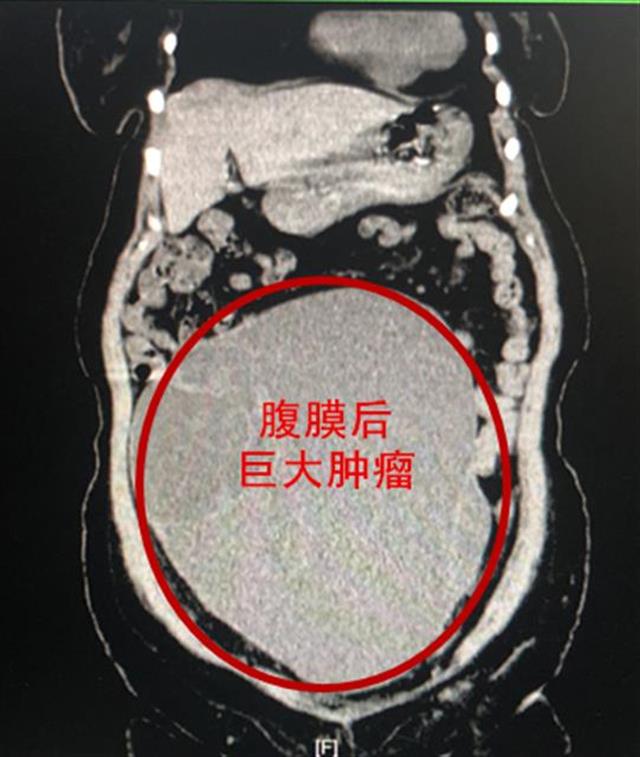

经详细查体并完善检查,接诊医师徐彦哲告诉张梅,导致一切不适的根源并非便秘,而是植根于腹膜后、位于中下腹部纵向26厘米、横径21厘米的巨大肿瘤压迫多处脏器所致。因瘤体体积过大,目前已使得患者胃肠、输尿管、肾脏、膀胱及下腔动静脉血管均受到严重挤压和压迫,因此才会产生明显的腹胀、无饥饿感、排便困难、少尿、双下肢浮肿等一系列症状。

为避免病症进一步加重甚至危及生命,该科曲波、徐彦哲团队为张梅进行了全麻下的腹腔镜微创手术,采用美容创口,从腹膜后的输尿管以及大血管表面仔细辨认、小心剥离,成功全切了这枚重达20斤的巨大腹膜后囊实性肿瘤。术后,张梅的腹胀感消失。目前,即将康复出院。